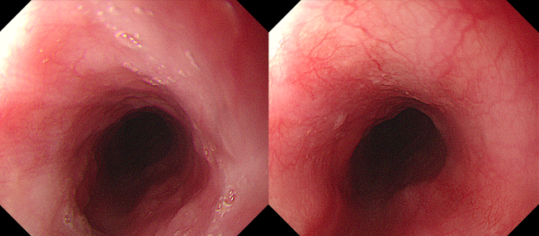

经过一个月细致的治疗和护理,乐乐目前恢复正常饮食,已经康复出院。复查胃镜显示,此前消化道黏膜的严重损伤和可疑穿孔处已完全愈合,食管也没有出现狭窄,黏膜状态几乎和损伤前一样,治疗效果远超预期。